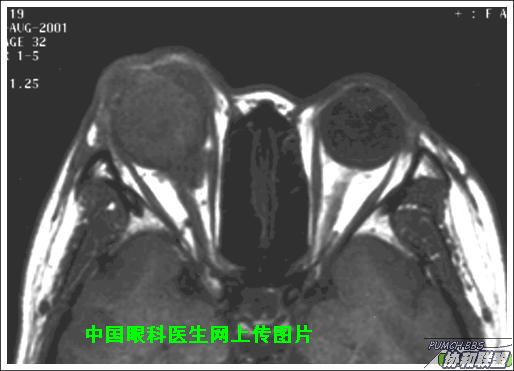

出院后半年发现右眼出现肿物,增长较快,随来京再次就诊(图1),转来我科。门诊检查发现:右眼无光感,结膜下肿物,突出睑裂。眼球突出,上移位。眶外侧可触及硬性肿物。超声(图2),CT(图3),MRI(图456)显示如图.